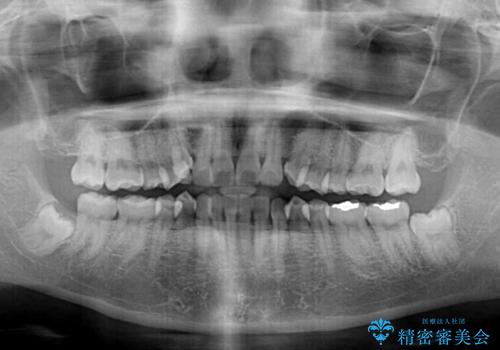

- 左右の八重歯を気にして来院された患者様です。

八重歯である犬歯は歯根が長いため、上顎前歯が出っ歯になるリスクがあるため、必要に応じてアンカースクリューを用いて奥歯を後方に移動させる可能性をお伝えしました。

舌の突出癖により上下前歯が開咬となりましたが、舌のトレーニングと顎間ゴムの使用により、元々の被蓋関係に改善することができました。

アンカースクリューを用いて、出っ歯仕上がりを回避し、正中位置も改善することができました。